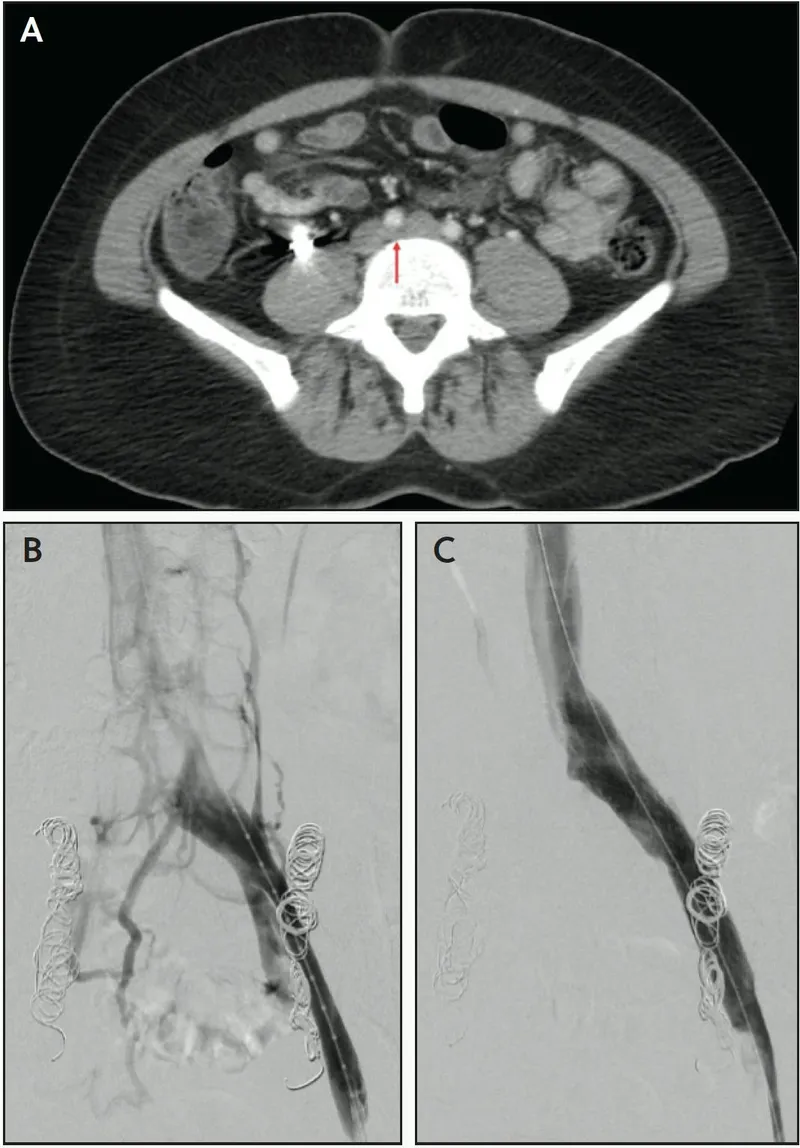

- Digital Subtraction Angiography (DSA):

- Invasive gold standard; diagnostic & therapeutic.

- Catheter-based, iodinated contrast, radiation.

- Enables angioplasty, stenting. Risks: access site.

⭐ DSA remains the gold standard for peripheral vascular imaging, especially when intervention is planned.